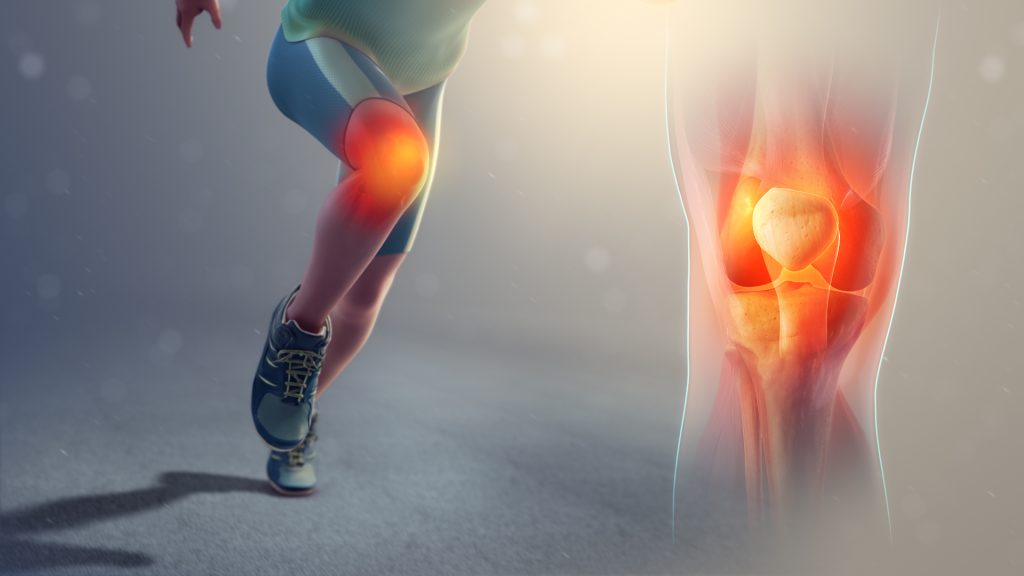

Sports Injuries

Sports injuries are physical damages that occur during athletic activities or exercise, often resulting from overuse, direct impact, or improper technique. Common types include sprains, strains, fractures, dislocations, and ligament...